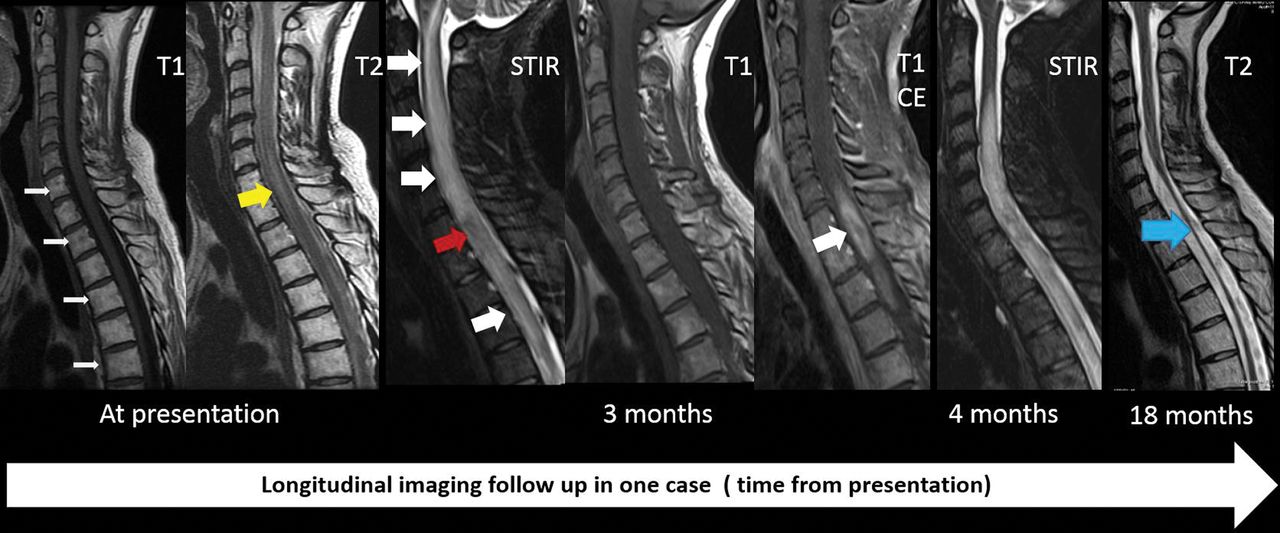

The mean duration from symptom onset to the first MR imaging was around 6 months (range, 0–41 months). Imaging findings summarized in Table 4 revealed that all 11 patients had at least 1 MR imaging that demonstrated cervical and/or thoracic cord lesions in a longitudinally extensive pattern (Fig 2), with T1 hyperintensity in the adjacent vertebrae included in the field of radiation (Fig 1A). T2 signal abnormalities predominantly involved the central cord on axial images. Involvement of the central two-thirds of the axial cord was noted in 4, the central and posterior cord was involved in 1, and the entire circumference of the axial cord was involved in 5 patients at their initial MR imaging (Fig 3). Cord expansion was seen in 6 patients, with prominent expansion in 3 (as evidenced by a completely effaced thecal sac circumferentially on axial T2-weighted images), and mild expansion in 3 patients. Contrast enhancement was variable and was seen in 45% of cases. Follow-up MR imaging (Table 5) was available for 8 (73%) patients (median, 14.5 months; range, 4–69 months). On follow-up MRIs, cord atrophy was noted in only 2 of 8 patients (25%). Persistent T2 abnormalities in the cord were noted in 4 of 8 (50%), while complete resolution of MR imaging findings was seen in 1 of 8 (12.5%). Hemorrhagic changes were noted in 1 of 8 (12.5%), with syringohydromyelia also noted in 1 patient (12.5%).

Our study is unique because follow-up imaging and clinical history were available in most of our patients, and on follow-up, cord atrophy was seen in only 25% of our cases, which suggests that the timing of MR imaging after radiation may dictate the imaging findings. One of the interesting observations in this study is resolution or a decrease in T2 signal changes (Fig 4), affecting 12.5% and 50%, respectively, on follow-up, especially because RM is thought to be irreversible and permanent. Although formal statistical analysis was not possible due to the rarity of occurrence and small sample size, our series suggests that clinical improvement may correlate well with imaging findings on longitudinal follow-up. Hemorrhagic changes, cord expansion, and contrast enhancement were variable and were noted in patients who were scanned early during the disease process, and tended to resolve on follow-up. This finding has not been well-reported, and our correlation with clinical history suggests that the extent of hemorrhagic changes may dictate the severity of neurologic symptoms at presentation and disability at follow-up.

Sequential changes on imaging in a patient with severe radiation myelitis. Fatty bone marrow changes present with hyperintense T1 signal involving C7 and the upper thoracic vertebrae on the first image (white arrows). Less extensive longitudinally extensive myelitis at the C7, T1, and T2 levels is noted on the T2-weighted image with hyperintense signal at presentation (yellow arrow). At 3 months, cord expansion and extensive T2/STIR hyperintense signal changes involving the cervical and upper thoracic cord are noted (white arrowhead) with contrast enhancement at the C7, T1, and T2 levels (single large white arrowhead). The patient was paraplegic with urinary and bowel incontinence. She was treated with a high dose of steroids. Follow-up images at 18 months show cord atrophy (blue arrow). She eventually was able to ambulate with a walker after extensive physical therapy. CE indicates contrast enhancement.